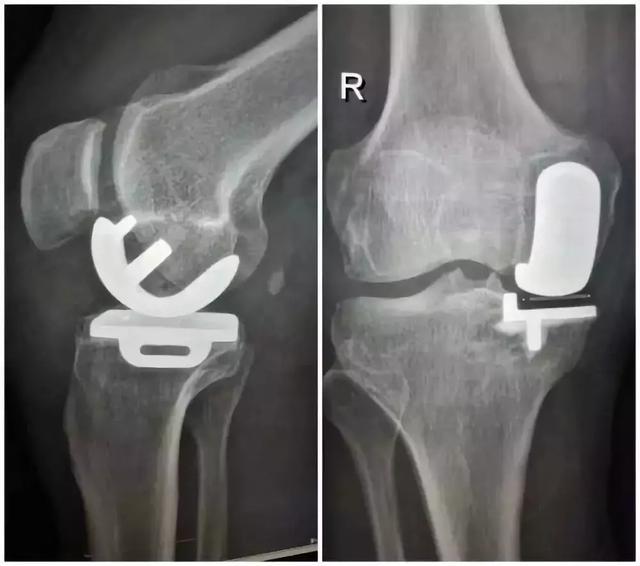

还有一种手术 , 我认为更好 , 但需要掌握时机 , 这就是单髁置换术!

文章插图

单髁置换术 , 可以阻断骨性关节炎的恶性循环进展 , 让患肢恢复正常功能!

一些患者的术后几天就可以扶助行器走路的情况!